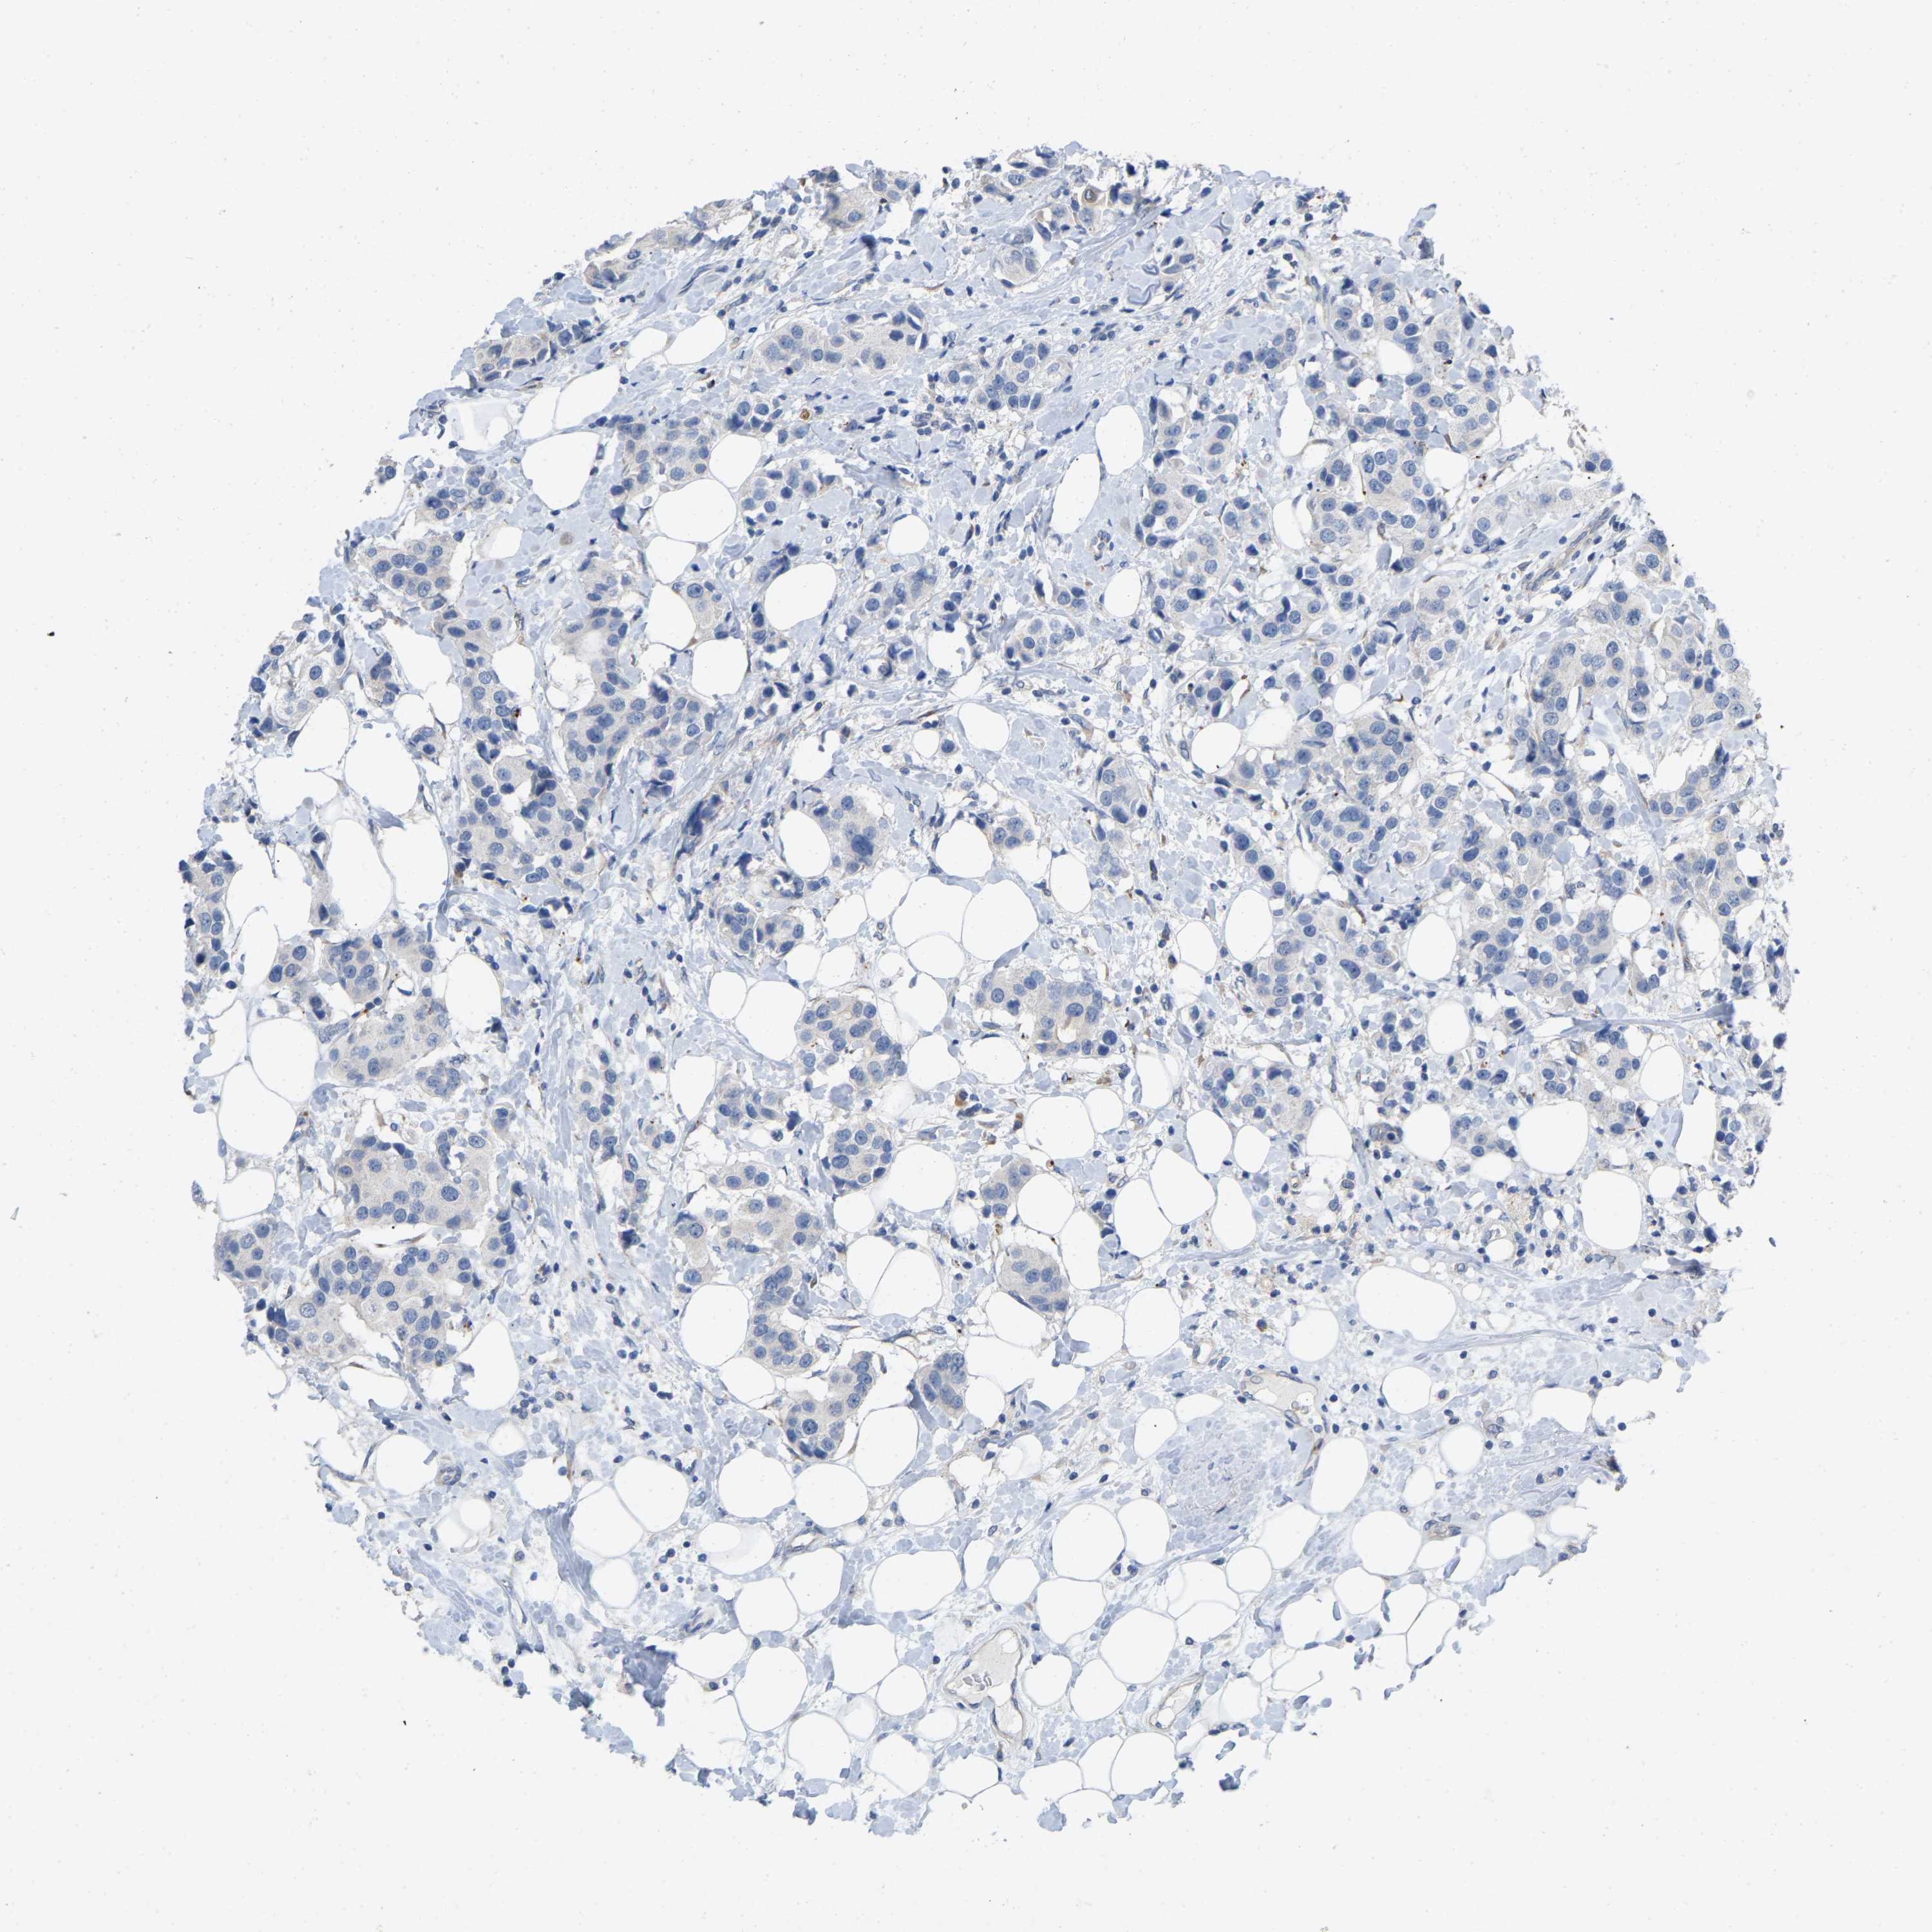

BRCA TCGA BRCA VALIDATION PROTEIN EXPRESSION

Breast cancer

Human cancer